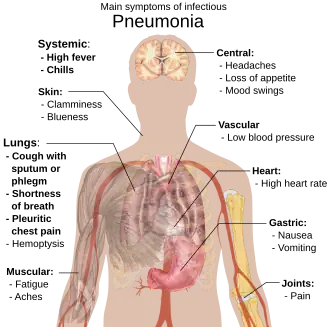

Signs and symptoms

Common symptoms

- Coughing which produces greenish or yellow sputum

- A high fever, accompanied by sweating, chills and shivering

- Sharp, stabbing chest pains

- Rapid, shallow, often painful breathing

Less-common symptoms

- Coughing up blood (hemoptysis)

- Headaches, including migraines

- Loss of appetite

- Excessive fatigue

- Bluish skin (cyanosis)

- Nausea

- Vomiting

- Diarrhea

- Joint pain (arthralgia)

- Muscle aches (myalgia)

- Rapid heartbeat

- Dizziness or lightheadedness